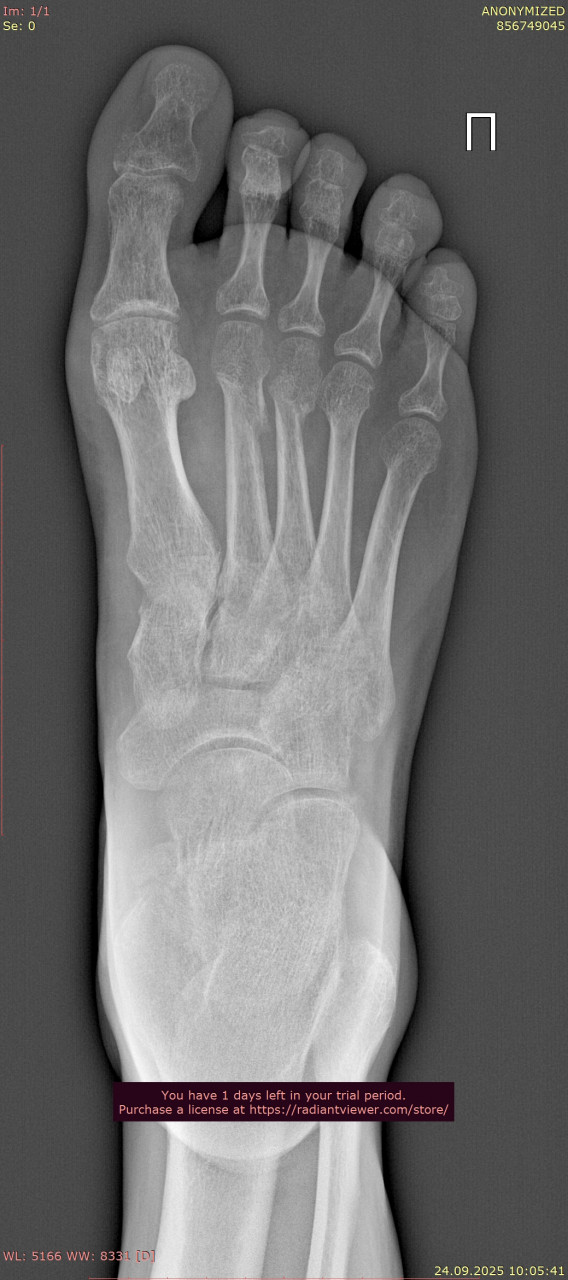

Прикрепляю снимки стопы от даты перелома 23.06.2025 (одна проекция из за лимита файлов на сайте} , и спустя 3 месяца от 24.09.2025. Как Вы считаете, переломы зажили окончательно, проблем быть не должно? В дополнение про выбор стелек: в ортопедическом салоне можно просто сказать, что у меня остеоартроз голеностопного сустава и попросить недорогие стельки по размеру?

Здравствуйте. На новых снимках переломы срослись, кость выглядит восстановленной, грубых осложнений не видно. Проблем при обычной нагрузке быть не должно. В салоне действительно можно сказать про остеоартроз голеностопа и подобрать недорогие готовые стельки по размеру и этого на начальном этапе будет достаточно.